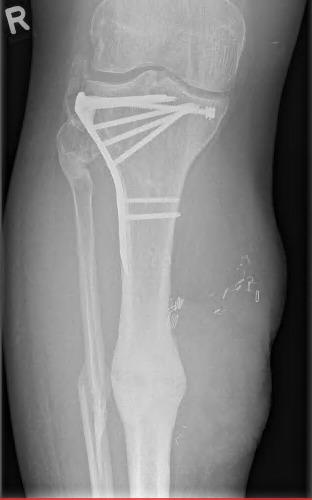

Multistep reconstruction of a post-traumatic defect in the lower limb with AV loop and free myocutaneous latissimus dorsi flap combined with a perforator monitor skin island after loss of ALT flap.

Crush injuries of the lower extremity with extensive osseous and soft tissue damage impose a big challenge even for an interdisciplinary reconstructive approach. Multistep reconstruction with negative wound pressure therapy for soft tissue management and external fixation for osseous stability preceding free flap transfer leads to optimized outcome. We report the successful multistep reconstruction of a third-degree open right tibial fracture with extensive soft tissue defect with an arteriovenous loop preceding latissimus dorsi flap coverage with a perforator skin island after loss of an anterior lateral thigh (ALT) flap due to intima damage of the recipient vessels. The described method is a safe reconstructive concept after primary flap loss with persistent extensive tissue damage.